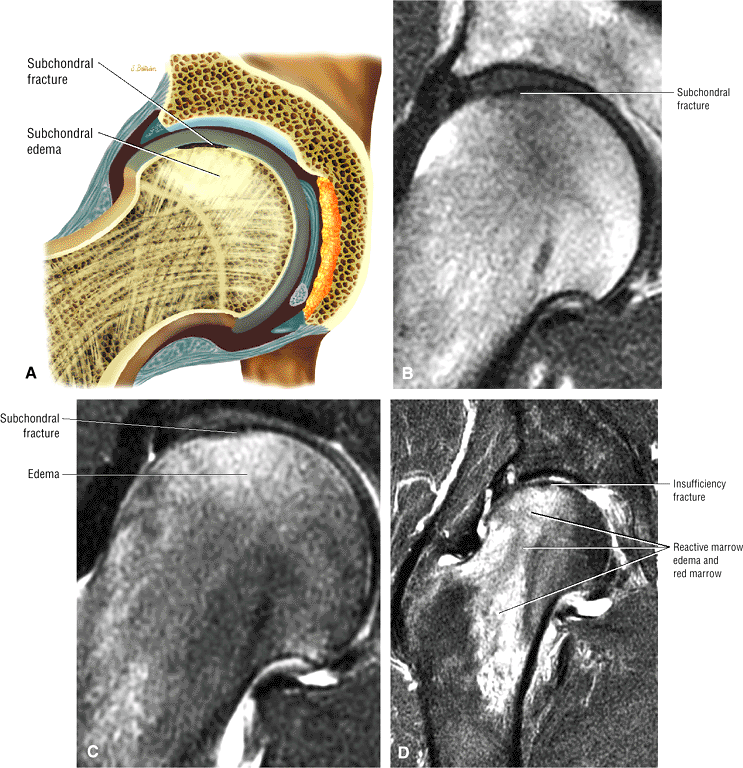

AVN usually involves the anterolateral aspect of the femoral head.

Sagittal images are the most accurate in assessing the femoral head changes that occur with subchondral fracture.

Many cases of previously diagnosed transient osteoporosis of the hip are, in fact, subchondral femoral head stress fractures.

Most cases actually represent subchondral femoral head stress fractures, which can be appreciated on small-FOV images.

A narrow line of sclerosis associated with a subchondral stress fracture

A hypointense fracture line parallel to the subchondral plate (high-resolution imaging is necessary for visualization)